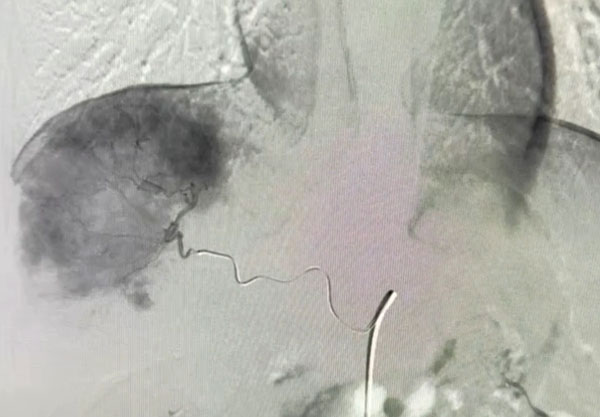

经周全的术前准备。手术于4月18日在杂交手术室实施。首先介入下行肿瘤供应血管置管(A7、A8)。介入手术由苟庆医生主刀,介入下找到肿瘤供应血管,并置管用作手术中造影。

紧接着的是腹腔镜下ICG引导肝部分切除术(S7、S8段切除)。肝胆外科林叶教授、黄凯军医生团队进行腹腔镜下ICG引导肝部分切除术,术中视野见所需切除的肝段完全染色,利用肿瘤的染色,精准的进行肝部分切除术。

肝S7、S8肝段完全染色